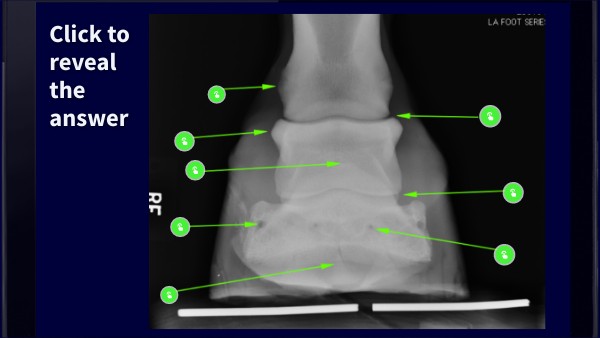

Lateral distal collateral tubercle of P1

Proximal interphalangeal joint

Lateral proximal collateral tubercle of P2

Distal interphalangeal joint

Extensor process

foramen of the lateral palmar/plantar process of distal phalanx

Medial solar foramen of the distal phalanx

Crena of the distal phalanx